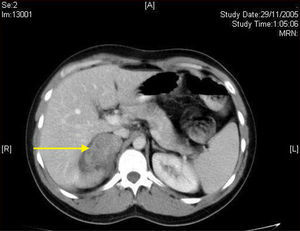

The first step in diagnosis always consists of hormone tests to show a non-functioning tumor: free cortisol in 24-h urine, suppression with dexamethasone 1mg, serum basal cortisol, ACTH, renin, plasma aldosterone, and catecholamines (epinephrine and norepinephrine) and their metabolites in blood and urine.3 The most helpful imaging tests are abdominal CT and magnetic resonance imaging (MRI), which have been shown to be superior to ultrasonography for the detection and characterization of adrenal disease.1 Gn is seen at CT as a well-defined, oval or lobulated solid mass with a low attenuation (usually less than 40 Hounsfield units) and a fibrous capsule (Fig. 1). Intratumoral calcifications are seen in 42–60% of cases, and may sometimes be heterogeneous after contrast administration.2,3,5,6 In MRI they show a low intensity signal in T1 and heterogeneity with high intensity in T2.5 Positron Emission Tomography (PET) has recently been incorporated to complement both tests in Gn diagnosis and, above all, to rule out malignant adrenal neoplastic conditions.1 Final diagnosis is made after histopathological analysis of the surgical specimen. The characteristic microscopic appearance is a uniform image with a stroma consisting of irregularly intertwined transversely and longitudinally oriented Schwann cells. Fat may occasionally be found. Relatively mature neurons with little Nissl substance and forming small groups or nests are found scattered throughout this Schwannian background. A bulky eosinophilic cytoplasm and one to three nuclei with mild to moderate atypia are typically seen (Fig. 2). The use of fine needle aspiration is limited by the possibility that the lesion is malignant (adrenal carcinoma or metastasis) or cystic in nature and by the difficulty in differentiating adenoma from carcinoma.2,3